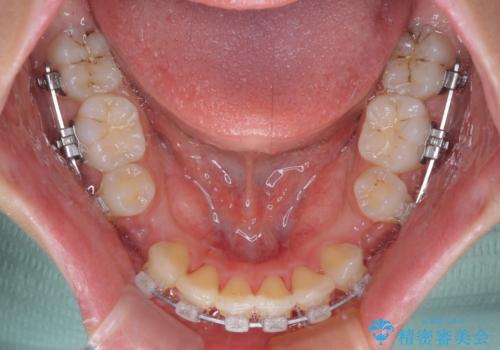

- クリアブラケット

下顎は叢生があったため、上下左右の第一小臼歯4本を抜歯し、更には口元の突出感を大きく改善させるために、上顎臼歯を後方に移動させるための補助装置をしようし、ワイヤー装置にて矯正治療を行うこととしました。